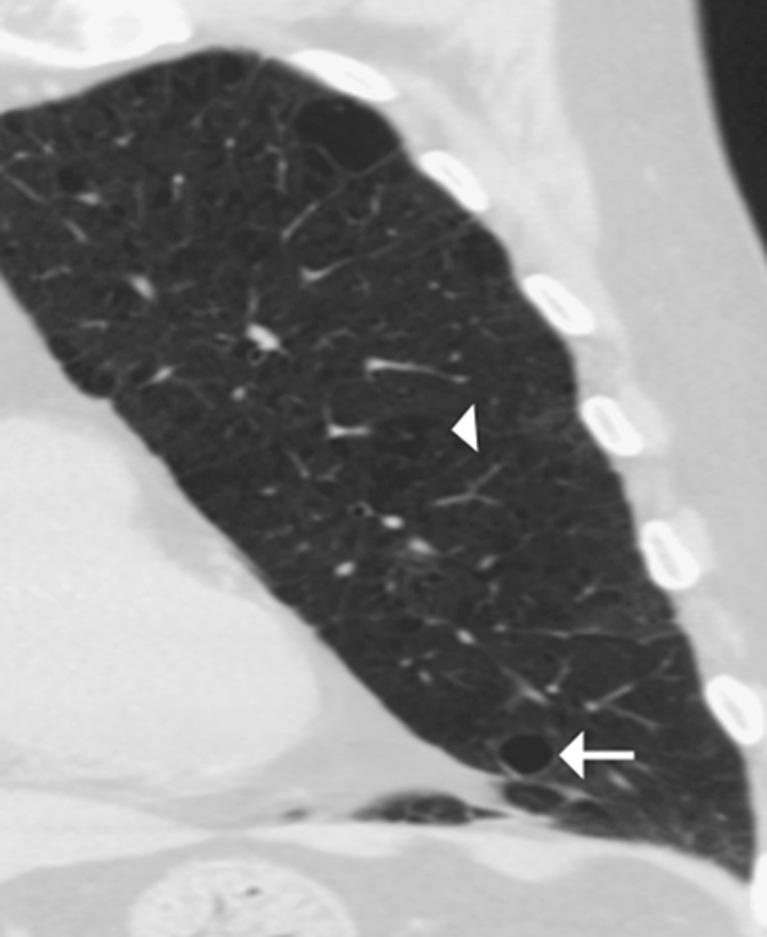

A lung cyst is defined as a round parenchymal lucency or area of low attenuation with a thin wall. They are not uncommon findings on high-resolution (HR) thoracic computed tomography (CT) and when identified, they require explanation. The differential diagnosis for diseases characterised by lung cysts is broad ranging from isolated chest disorders to rare multisystem diseases. This article provides a practical approach for evaluating lung cysts on HRCT, highlighting disorders in which the HRCT findings can be diagnostic as well as conditions where correlation with clinical history or biopsy is required.

肺囊肿被定义为圆形的实质透亮区或具有薄壁的低衰减区域。它们在高分辨率(HR)胸部计算机断层扫描(CT)上并非罕见的发现,一旦被识别,就需要进行解释。以肺囊肿为特征的疾病的鉴别诊断范围广泛,从孤立的胸部疾病到罕见的多系统疾病。本文提供了一种在HRCT上评估肺囊肿的实用方法,重点介绍了HRCT表现具有诊断价值的疾病以及需要结合临床病史或活检的情况。